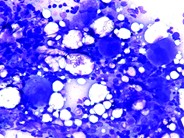

Blood smear showing proplatelet in the peripheral blood of a patient with myelodysplastic syndrome (arrow), May-Grünwald-Giemsa stain.